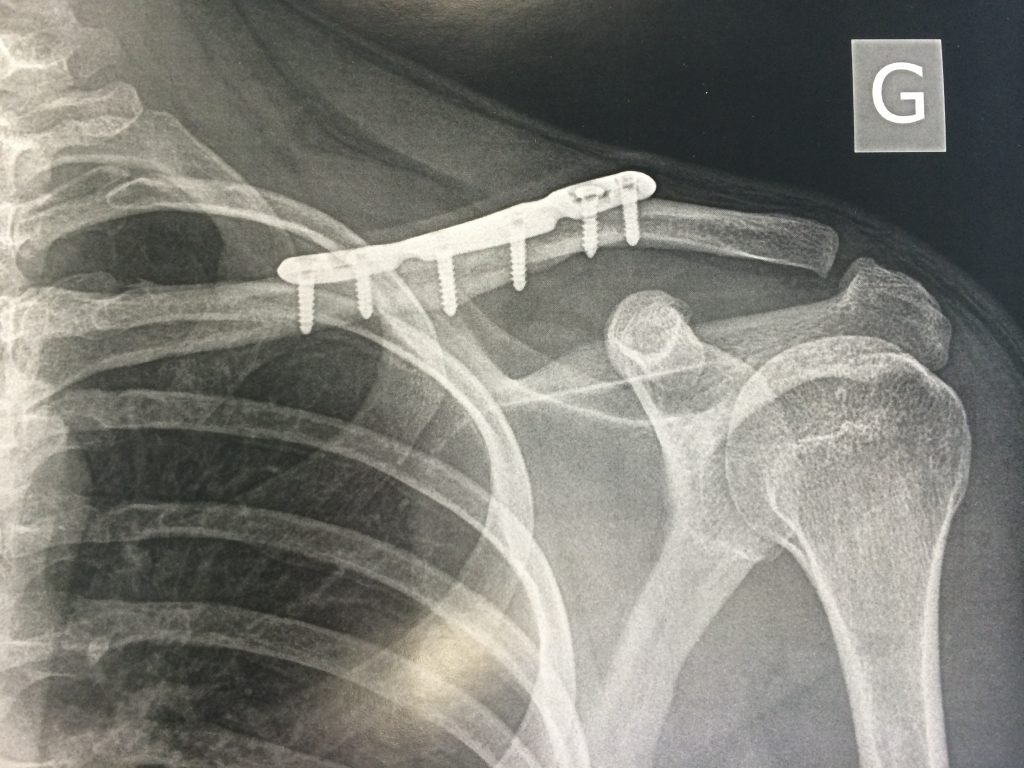

Clavicule Cassee Temps Guerison. La reprise du sport peut être plus longue. la fracture de la clavicule est une cassure du long os qui est horizontale entre la partie supérieure du sternum et la partie supérieure de l’omoplate. Dans cet article nous ajoutons des précisions sur la durée. le temps de guérison d’une clavicule cassé est d’environ 6 semaines. ⏱️ temps de guérison et récupération après une fracture de la clavicule. Tous ces délais sont raccourcis chez l’enfant et l’adolescent. 🚭 comment maximiser les chances de consolider vite et bien ? en général, il faut bien 6 à 10 semaines pour guérir d’une clavicule cassée. La douleur diminue en général assez rapidement au repos, mais peut durer plusieurs semaines lors des mouvements de l’épaule. L’immobilisation de la clavicule dure selon le type de fracture de 3 à 6 semaines. la durée varie en fonction de plusieurs facteurs, peut aller de 6 à 12 semaines (3 mois). Toutefois, si votre clavicule a été déplacée ou nécessite une intervention chirurgicale pour être réparée, la période de récupération peut être beaucoup plus longue et nécessiter des soins complémentaires.